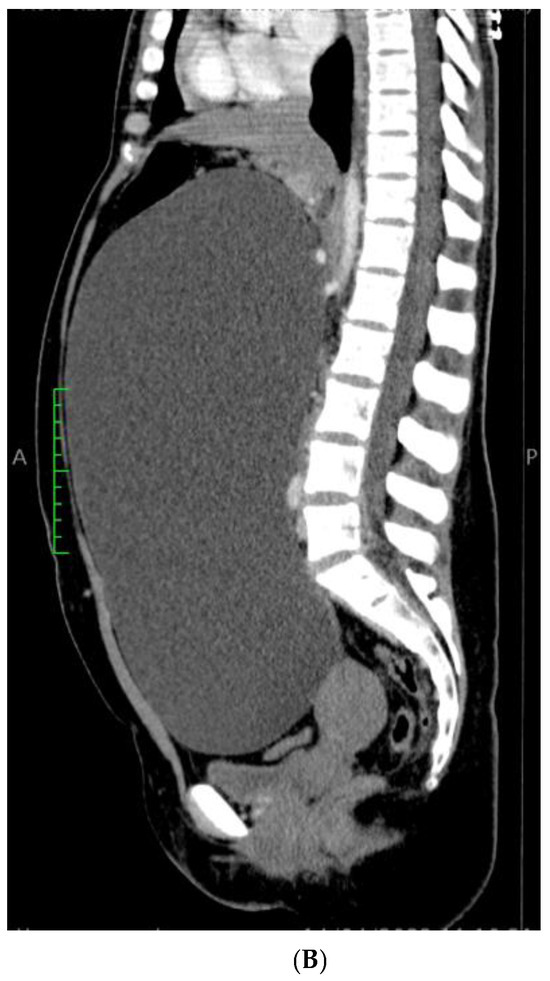

A 21-year-old, nulliparous, virgin woman presented to the Gastroenterology Department with the acute onset of upper abdominal pain but without any other symptoms such as chronic pain, abdominal distension, weight gain, or intra-abdominal pressure. She is a White/Caucasian woman from a rural environment with no medical history, and she lacked family history data. Moreover, the patient did not have any urinary or bowel symptoms. Her menstrual cycle was regular and normal, with her last menstrual period 3 weeks prior to hospital admission. Her full blood count was normal, and the microscopic examination of the urine sediment and urine culture did not show evidence of urinary tract infection. A urine pregnancy test was not performed due to the fact that she had never had intercourse. She had not received any treatment prior to the gynecological examination. The patient’s weight was 79 kg. Abdominal inspection mimicked a term pregnancy (Figure 1), and bimanual pelvic examination was not performed. Abdominal ultrasound performed at another medical facility revealed a simple cystic mass that was difficult to measure. No Doppler flow was detected, no septa nor papillary projections were noted, and there was no ascites. The left ovary appeared normal with only a 20 mm follicle. CA125, CEA, and CA 19-9 levels were within normal limits. The patient did not have immediate access to Magnetic Resonance Imaging (MRI), so she was referred for computer tomography (CT) examination which revealed a gigantic abdominal cystic mass of 150/300/360 mm (antero-posterior/transversal/cranio-caudal), most probably of ovarian origin with a thin wall with no septum or calcification that moves the retroperitoneal structures and compresses the bowel. The right ovary could not be observed. The left ovary measured 39/26 mm and presented few follicles, the largest being 26 mm. There were no abnormalities in the uterus, intraperitoneal fluid was absent, and no abnormal lymph nodes were identified. All other structures were within normal limits (Figure 2A,B).

Figure 2. CT Scan: Gigantic ovarian cyst of 360/300/150 mm. (A) Sagittal section and (B) coronal section.